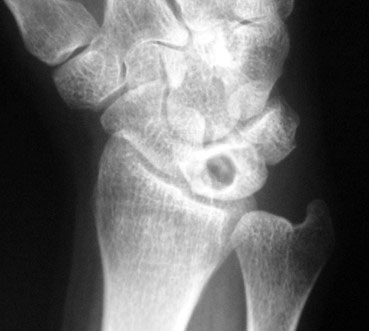

Radiografía simple.

La radiografía puede mostrar cambios en la densidad del semilunar, esclerosis, pérdida de altura, colapso o signos degenerativos en fases más avanzadas. También puede ayudar a identificar variantes anatómicas asociadas, como el cúbito corto.

La clasificación más utilizada es la clasificación de Lichtman, que divide la enfermedad en distintos estadios clínico-radiológicos y orienta el tratamiento.

Estadio I

La radiografía puede ser normal, pero la resonancia ya muestra alteraciones relacionadas con la falta de riego sanguíneo del semilunar.

Estadio II

Aparece esclerosis radiológica del semilunar, aunque su forma todavía se conserva.

Estadio III

El semilunar empieza a colapsarse y se distinguen dos subtipos.

Estadio IIIA

Existe colapso del semilunar, pero se mantiene mejor la arquitectura general del carpo.

Estadio IIIB

Además del colapso, aparece alteración de la alineación carpiana, como rotación fija del escafoides o colapso del carpo.

Estadio IV

Existe una afectación avanzada, con destrucción del semilunar y cambios degenerativos artrósicos en la muñeca.